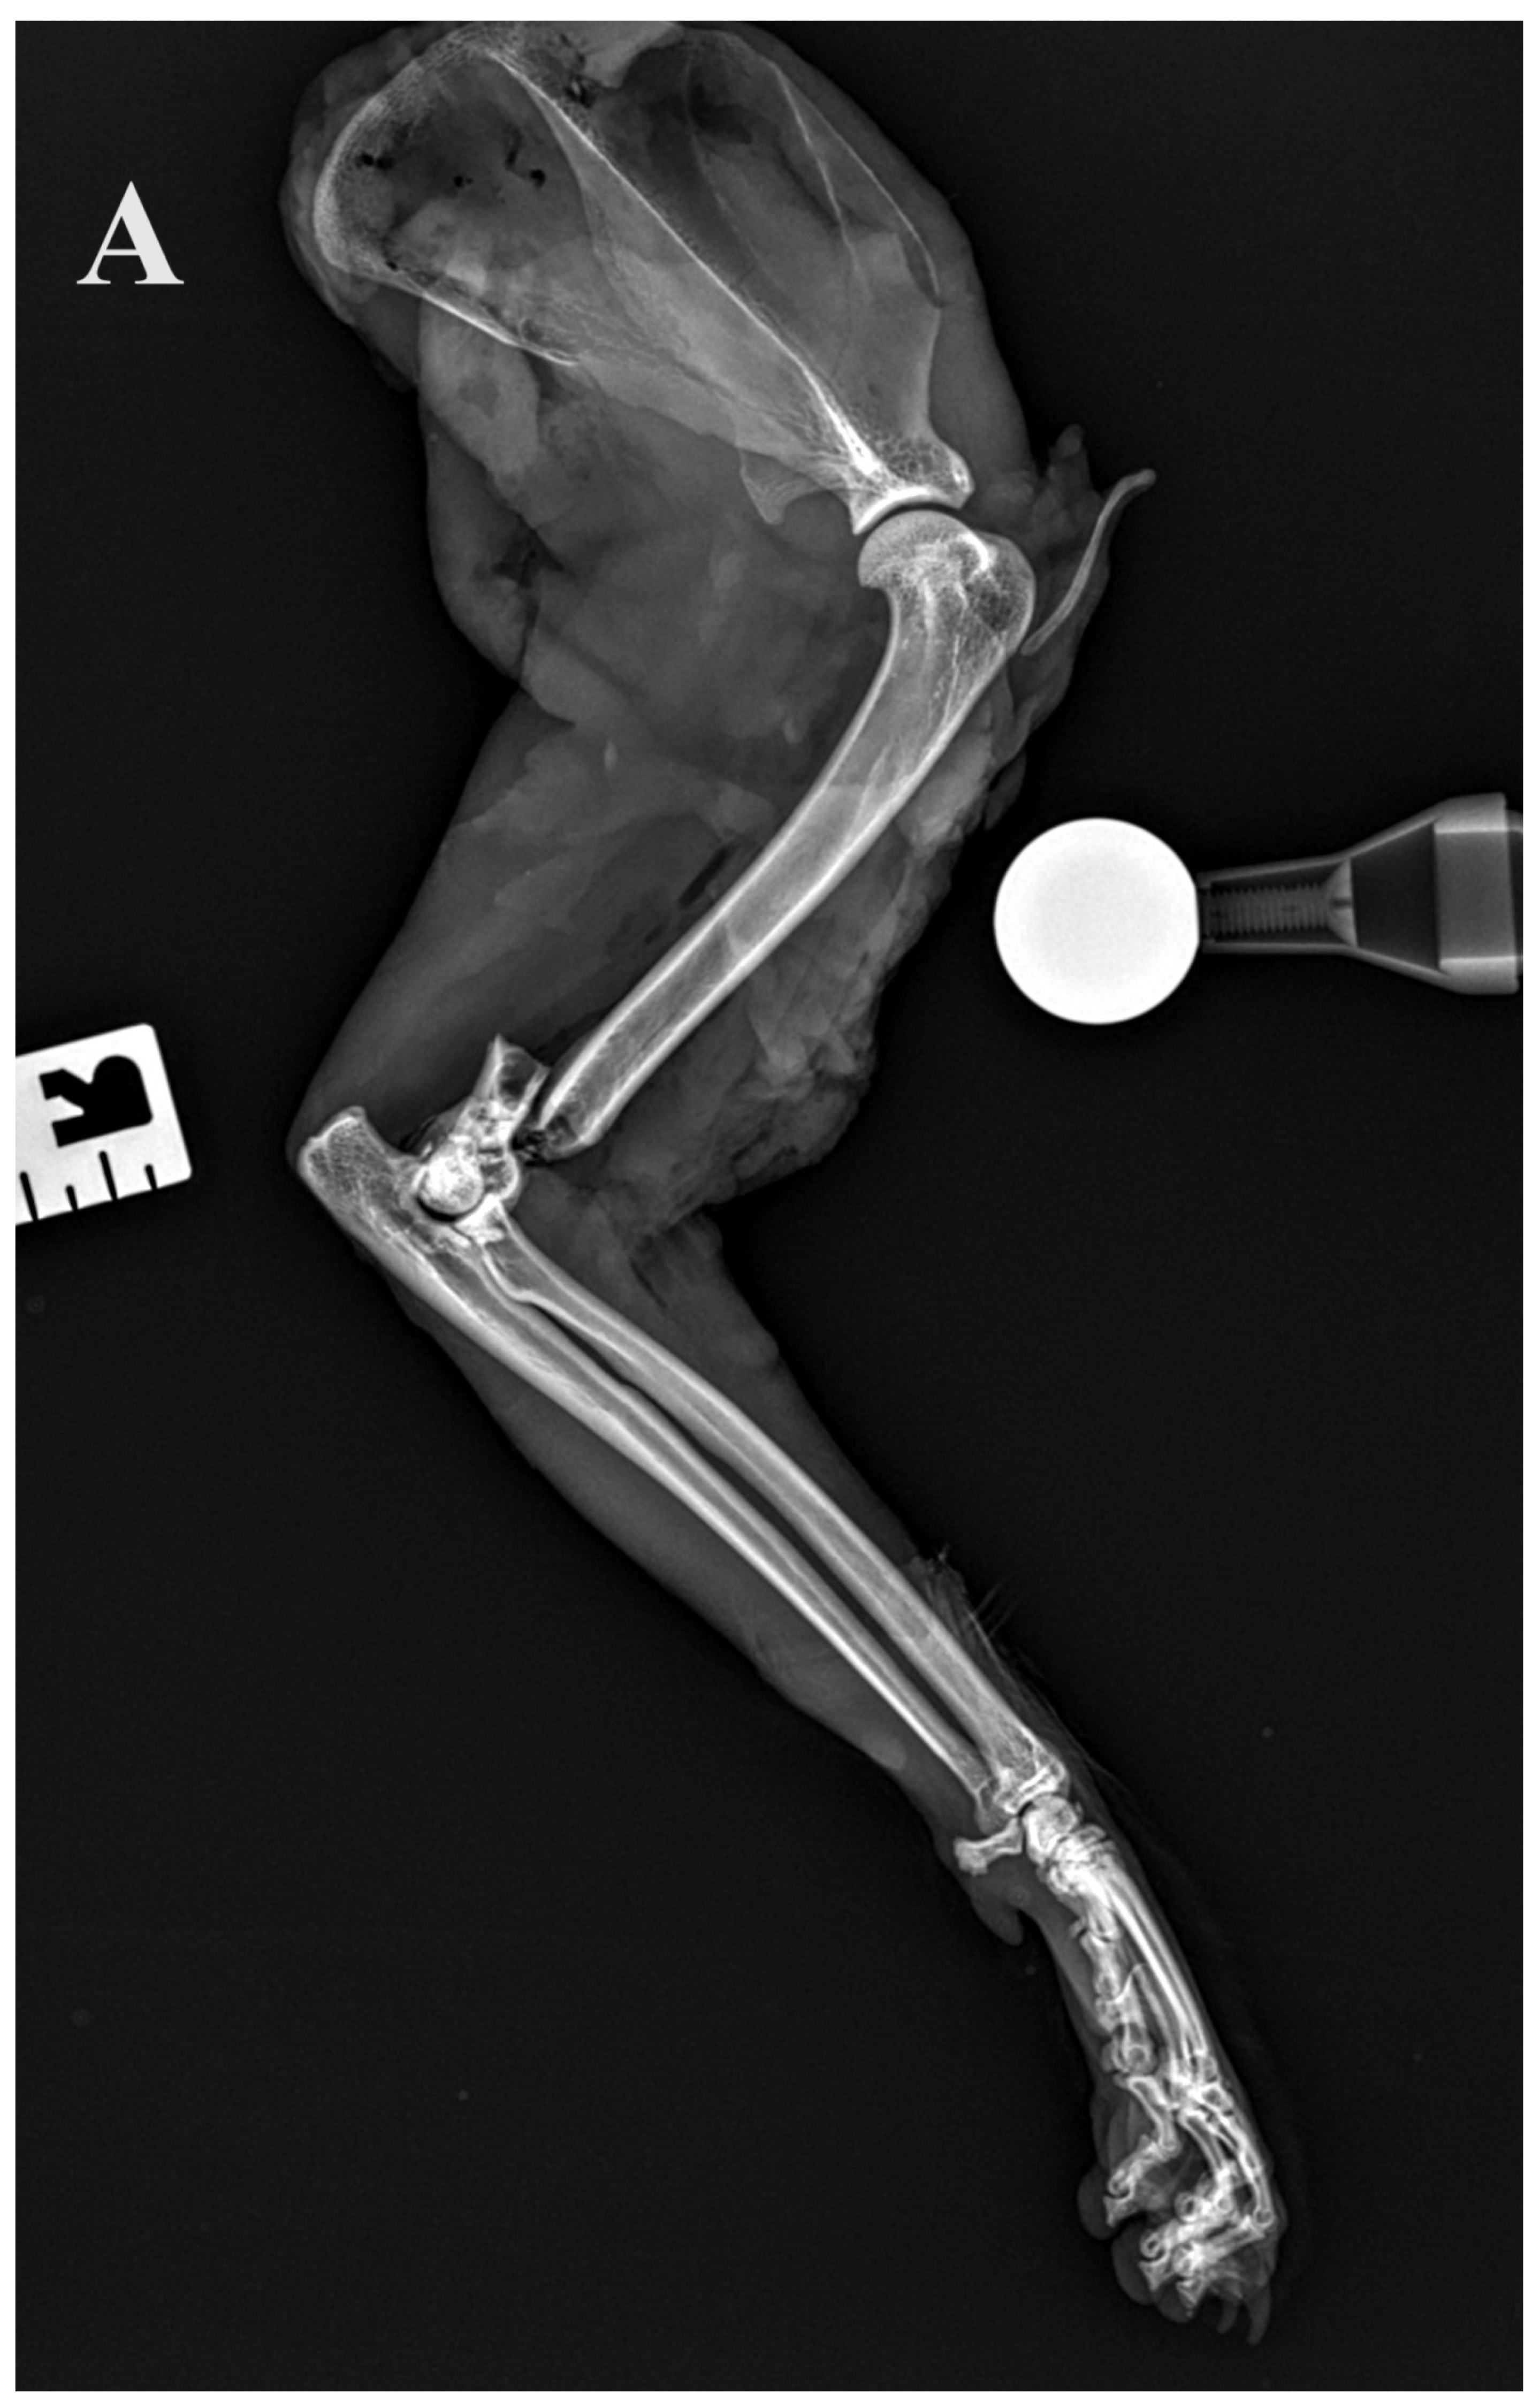

2.3. Radiographic Assessment

Standard calibrated orthogonal radiographs of the amputated limbs were assessed before and after the Y-T fracture creation. For each limb, the length of the humerus, the diameter of the isthmus of the humeral condyle measured on the cranio–caudal radiographs and the fracture configuration were assessed. The implants and repair were assessed on postoperative radiographs. The accuracy of articular surface reduction and the resulting articular surface defect were measured and graded as small (<1 mm), moderate (1–2 mm) or large (>2 mm). In addition, alignment (axial and rotational alignment of the joints above and below the fracture), adjacency (adequate attachment of the main fracture fragments to the comminution zone) and apparatus (implants’ location, placement, security and size) were assessed.

Figure 5.

(A,B) Initial lateral and cranio–caudal radiographs of the right forelimb of a female domestic cat show a displaced Y-T fracture. (C,D) Postoperative lateral and cranio–caudal radiographs show a small articular surface defect (<1 mm) of humeral condyle and adequate alignment, adjacency and apparatus (2.0/2.4/2.7 3D printed plate, 2.4/2.7 straight interlocking bone plate and screws).